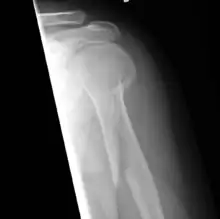

Fractura espiroidea

En medicina y traumatología, se designa con el nombre de fractura espiroidea a aquella fractura ósea en la cual la línea de fractura sigue una dirección espiral en relación al eje principal o longitudinal del hueso. Se llama en ocasiones fractura por torsión en base al mecanismo de producción. Afecta fundamentalmente a los huesos largos como el húmero y la tibia.[1]